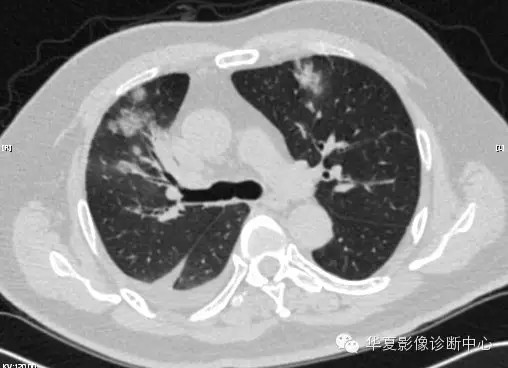

【病例学习】甲型H7N9禽流感一例

男性 63

发热咳嗽5天

2013-4-5拍片示右肺实变,收入院,追问病史,发病期间肌肉酸痛,头痛,无腹痛腹泻,无明显胸闷气急,无意识改变。有高血压病史,无其它病史。

2013-4-7CT进一步检查。

最终诊断:H7N9。